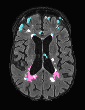

In recent years, data-driven machine learning (ML) methods have revolutionized the computer vision community by providing novel efficient solutions to many unsolved (medical) image analysis problems. However, due to the increasing privacy concerns and data fragmentation on many different sites, existing medical data are not fully utilized, thus limiting the potential of ML. Federated learning (FL) enables multiple parties to collaboratively train a ML model without exchanging local data. However, data heterogeneity (non-IID) among the distributed clients is yet a challenge. To this end, we propose a novel federated method, denoted Federated Disentanglement (FedDis), to disentangle the parameter space into shape and appearance, and only share the shape parameter with the clients. FedDis is based on the assumption that the anatomical structure in brain MRI images is similar across multiple institutions, and sharing the shape knowledge would be beneficial in anomaly detection. In this paper, we leverage healthy brain scans of 623 subjects from multiple sites with real data (OASIS, ADNI) in a privacy-preserving fashion to learn a model of normal anatomy, that allows to segment abnormal structures. We demonstrate a superior performance of FedDis on real pathological databases containing 109 subjects; two publicly available MS Lesions (MSLUB, MSISBI), and an in-house database with MS and Glioblastoma (MSI and GBI). FedDis achieved an average dice performance of 0.38, outperforming the state-of-the-art (SOTA) auto-encoder by 42% and the SOTA federated method by 11%. Further, we illustrate that FedDis learns a shape embedding that is orthogonal to the appearance and consistent under different intensity augmentations.